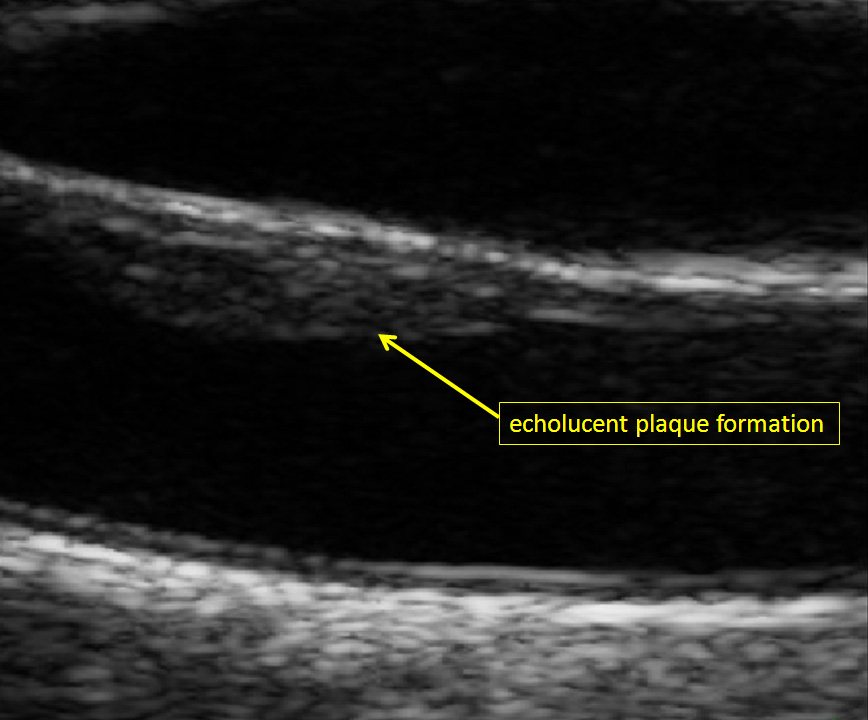

Figure 2

Echolucent carotid plaque formation at the near wall of the right common carotid artery (male study participant of the population-based Heinz Nixdorf Recall study) [19].

The last three decades, quantification and evaluation of carotid plaque formation has changed remarkably. In addition to cursory assessments like degree of stenosis and echogenicity, other distinctive features have been used to investigate carotid plaques. The most common used criteria for plaque investigation are echogenicity (echolucent, echogenic, mixed echogenicity), echogenic distribution pattern (homogeneous versus inhomogeneous) and evaluation of surface structure (regular versus irregular). Furthermore, measurement of two dimensions (2D) and three-dimensions (3D) are used to quantify total plaque area and total plaque volume [53, 54]. Lastly, plaque vascularisation on contrast-enhanced ultrasound are developed to optimise cardiovascular risk prediction [55, 56]. Because the prevalence of carotid plaques in a population at 60 years is 60%–90% [57] it seems to be of additional benefit for risk prediction to take this different ultrasound derived pattern into consideration at least in an elderly population. Finally both, quantification of CIMT and carotid plaque formation provide different information of the atherosclerotic status and burden in the carotid artery. Taken together these two parameters have been shown to result in a superior risk prediction for coronary heart disease than with one of the parameters alone [15].